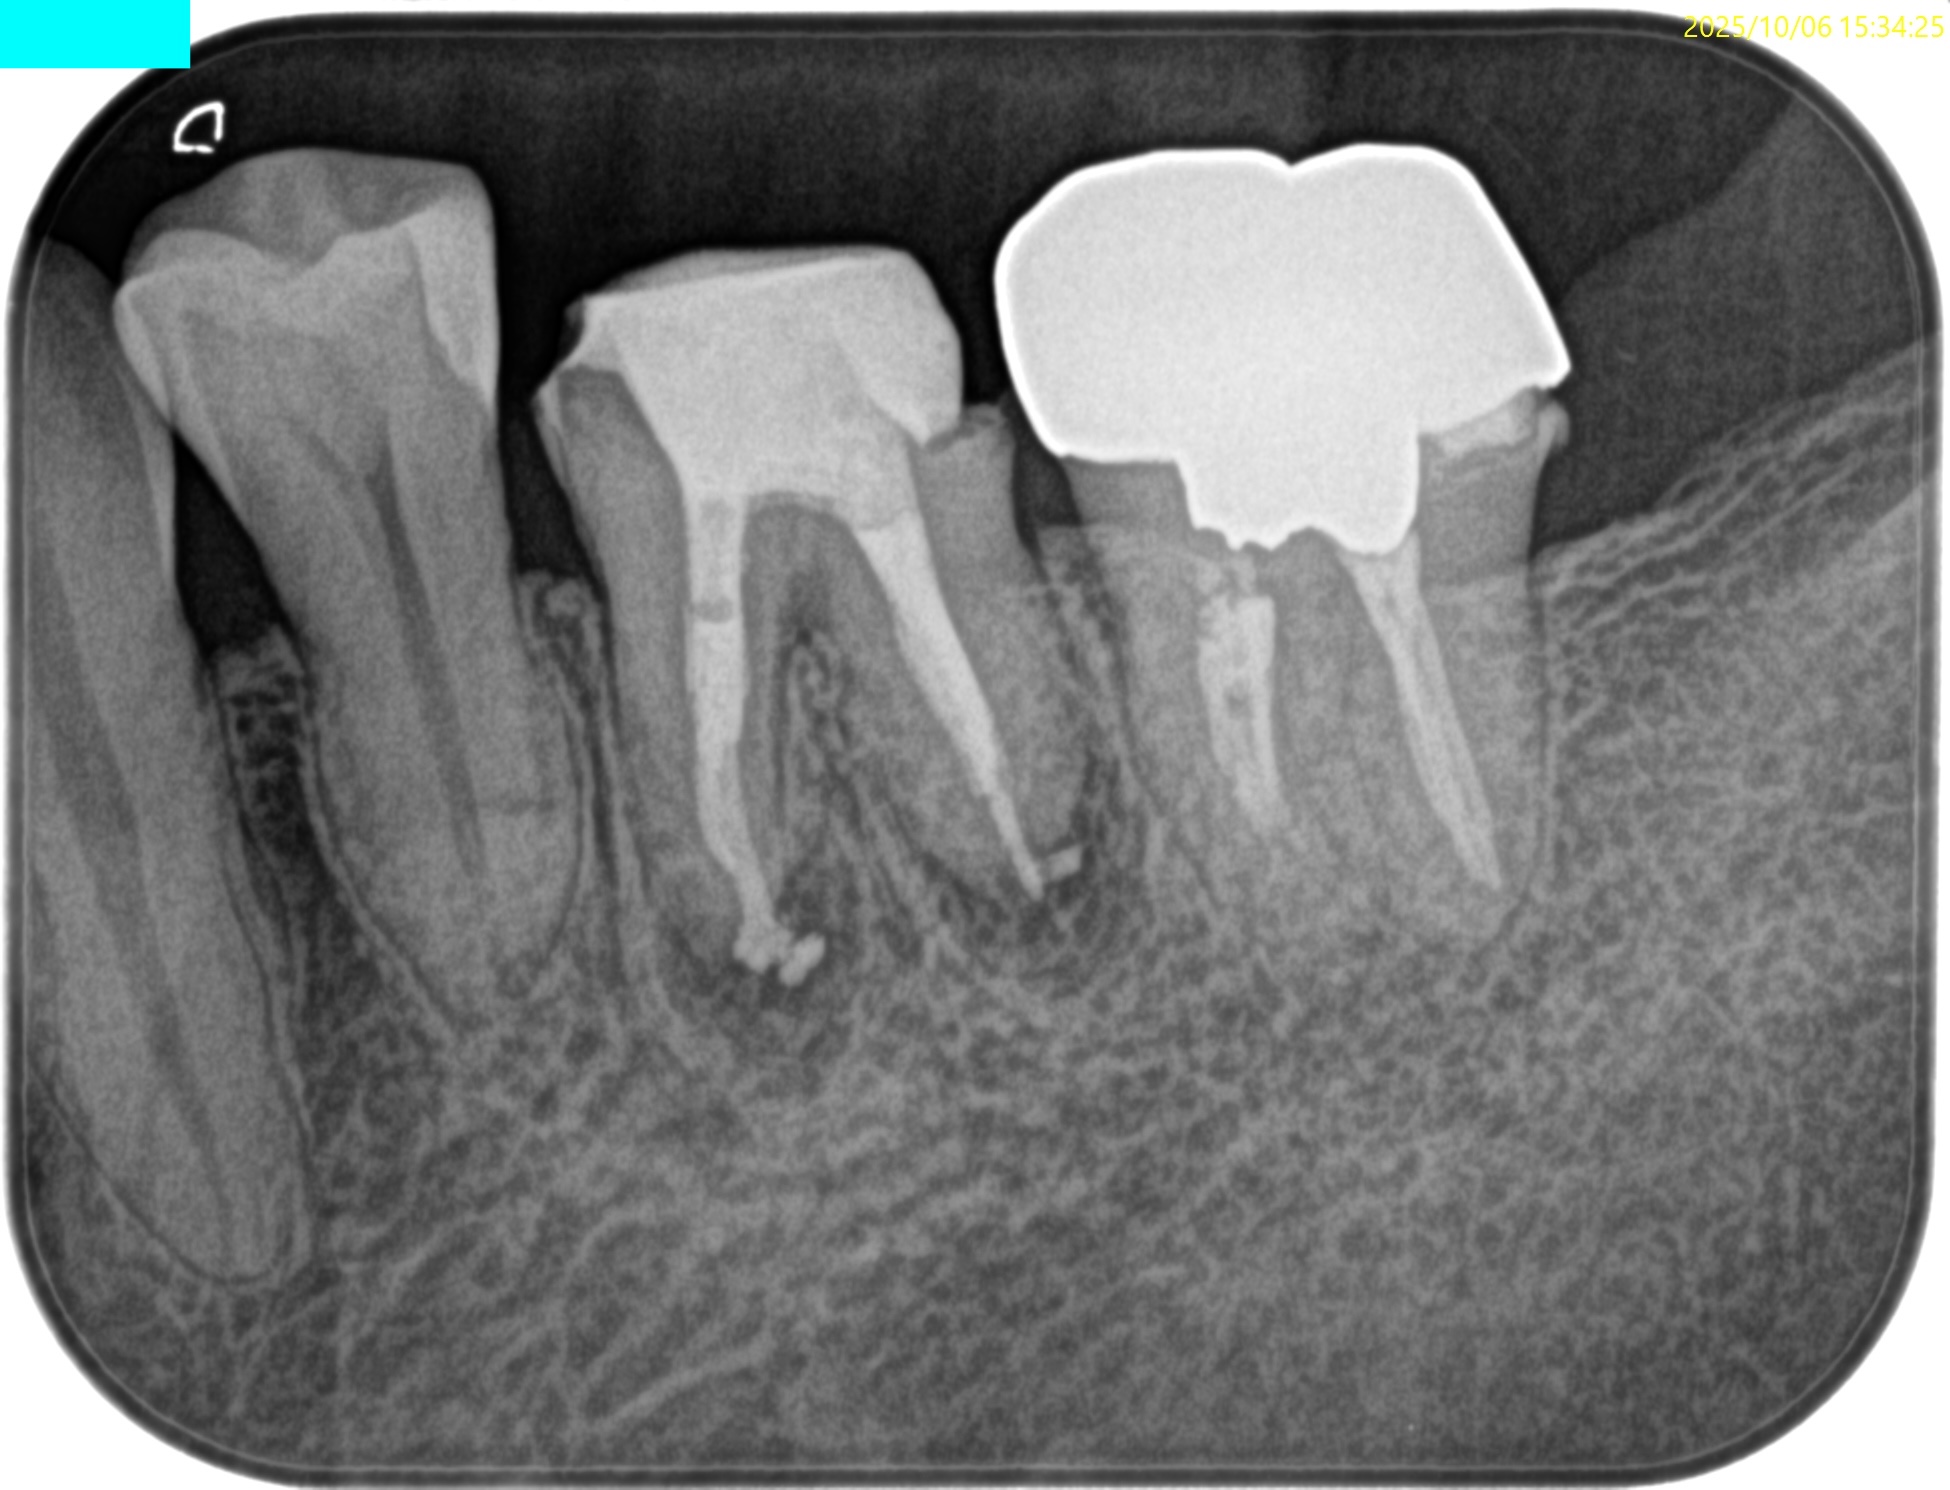

#19 Re-RCT(2025.10.6)

再根管治療は以下のように作業した。

術後にPA, CBCTを撮影した。

MB

ML

D

B